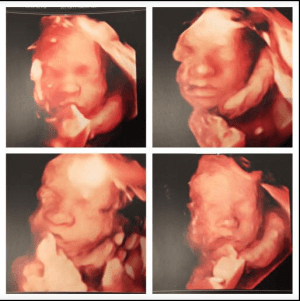

freddie 4d